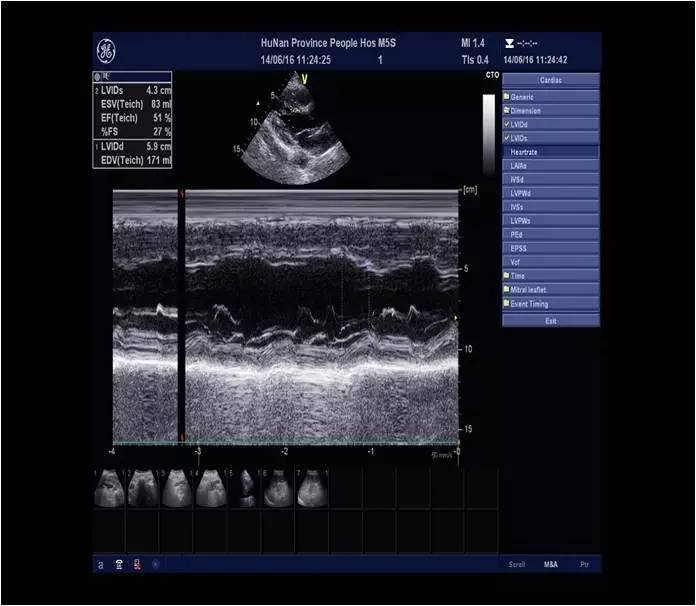

诊断结论:左房高值,左室增大,心功能:EF:28%(Simpson法),室壁运动普遍明显减弱,收缩功能测值明显减低。

AO窦部:42mm AAO:38mmLA:31mm LV:DM:48mm SM:35mmPA:22mm RA:26mm RV:26mm IVS:14mm LVPW:12mm

心功能:EF:51%;FS:27%

a.主动脉窦部及升主动脉内径增宽

b.左室壁增厚、运动不协调

c.二尖瓣、三尖瓣轻度返流

d.主动脉瓣轻-中度返流

e.左室舒张功能减退、收缩功能测值偏低

2.本例患者心梗40天后复查,心脏超声LVEF 51%,LVDM 48mm,心功能Ⅱ级,可不植入ICD。